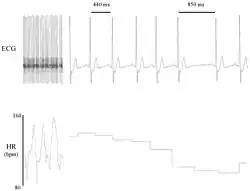

Heart rate variability (HRV) is the physiological phenomenon of variation in the time interval between heartbeats. It is measured by the variation in the beat-to-beat interval.

Other terms used include "cycle length variability", "R–R variability" (where R is a point corresponding to the peak of the QRS complex of the ECG wave; and R–R is the interval between successive Rs), and "heart period variability".[1] Measurement of the RR interval is used to derive heart rate variability.[1]